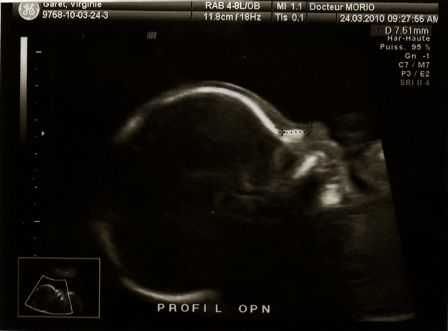

Bébé à 3 mois de grossesse

Par Virginie et Julien Garet le samedi, mai 15 2010, 20:59